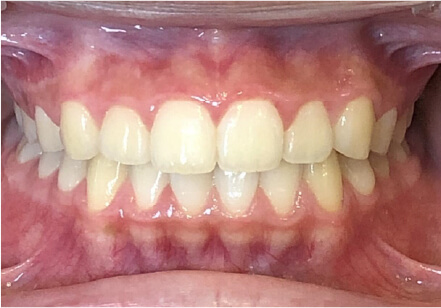

過蓋咬合の症例

15歳

/

女性

相談内容

前歯と前歯が噛んでいない

カウンセリング・診断結果

過蓋咬合

治療内容・方法

全額アライナー矯正

術後の経過・現在の様子

クリアライナー使用

治療のリスク

痛み・歯根吸収・歯肉退縮・虫歯・後戻り

費用・治療期間

830,000円、2年